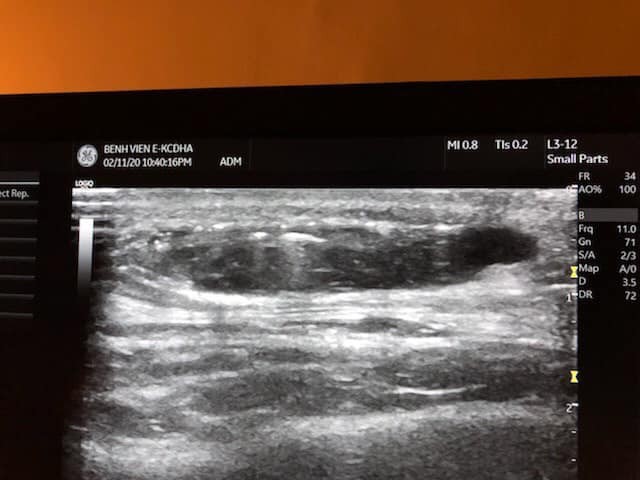

Phim chụp của bệnh nhân. Ảnh: Bệnh viện E

Ngay sau khi bệnh nhân nhập viện, ThS. BS. Nguyễn Đình Minh đã chỉ định siêu âm phát hiện thái dương bên trái có khối tụ dịch cách bề mặt da 3mm, kích thước 35 x 8 mm; vùng bên phải đã đặt chất liệu, không tụ dịch.